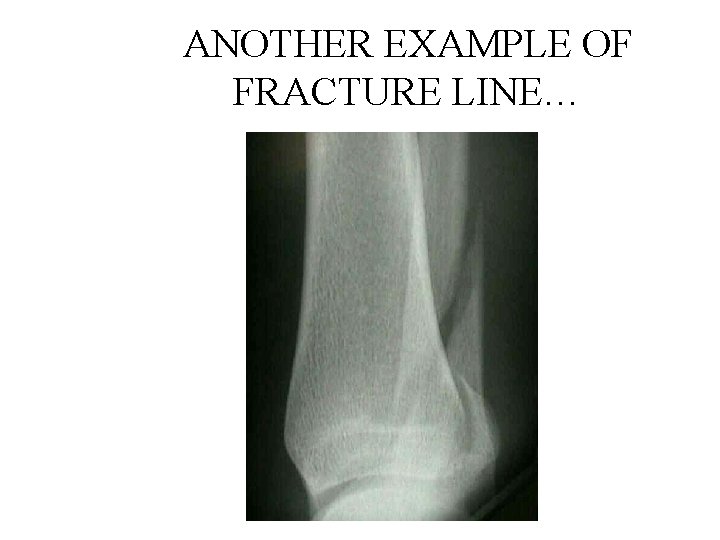

ANOTHER EXAMPLE OF FRACTURE LINE…

ANS: SPIRAL FRACTURE • Spiral fractures occur in a spiral fashion along the long axis of the bone • They are usually caused by a rotational force • To fully describe the fracture, this is a closed distal spiral fracture of the fibula